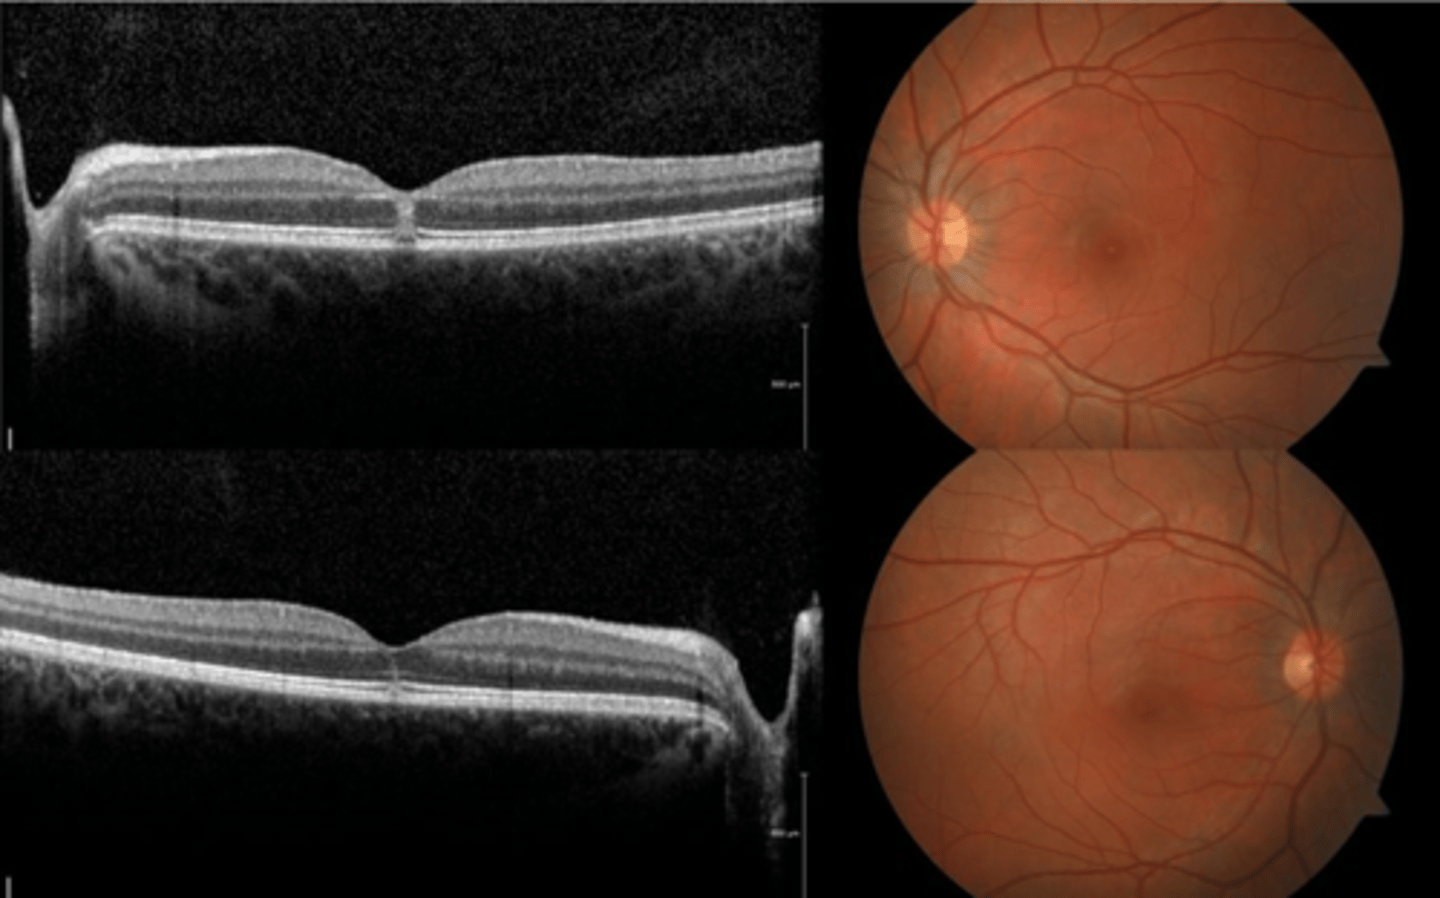

How does choroidal rupture appear on OCT here?

loss of RPE continuity at site of rupture = inner choroid atrophy

How does choroidal rupture appear on OCT here?

RPE disruption

+/- hemorrhage